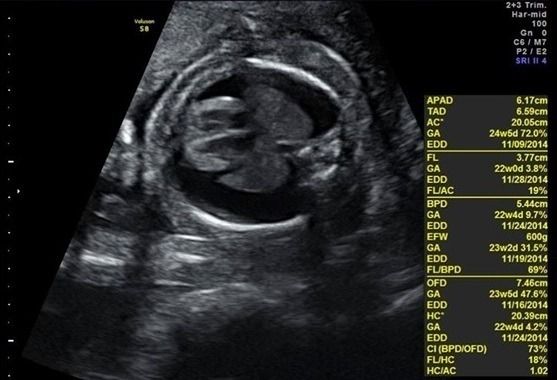

還記得,這對爸媽來到我門診的時候,是懷孕二十幾周的事了,來的時候寶寶超音波照片是長這樣:

治療前

胎兒雙側乳麋胸合併胎兒水腫。